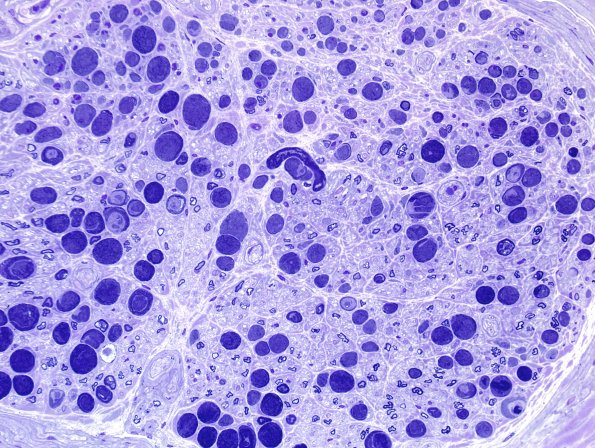

Washington University Experience | PERIPHERAL NEUROPATHY | 0 PNS ARTIFACTS | 12D2 Artifact, crush First sections Plastic 40X 2a.jpg

Marked involvement of the first sections by crush artifact. (Toluidine blue stained one micron thick plastic embedded sections)